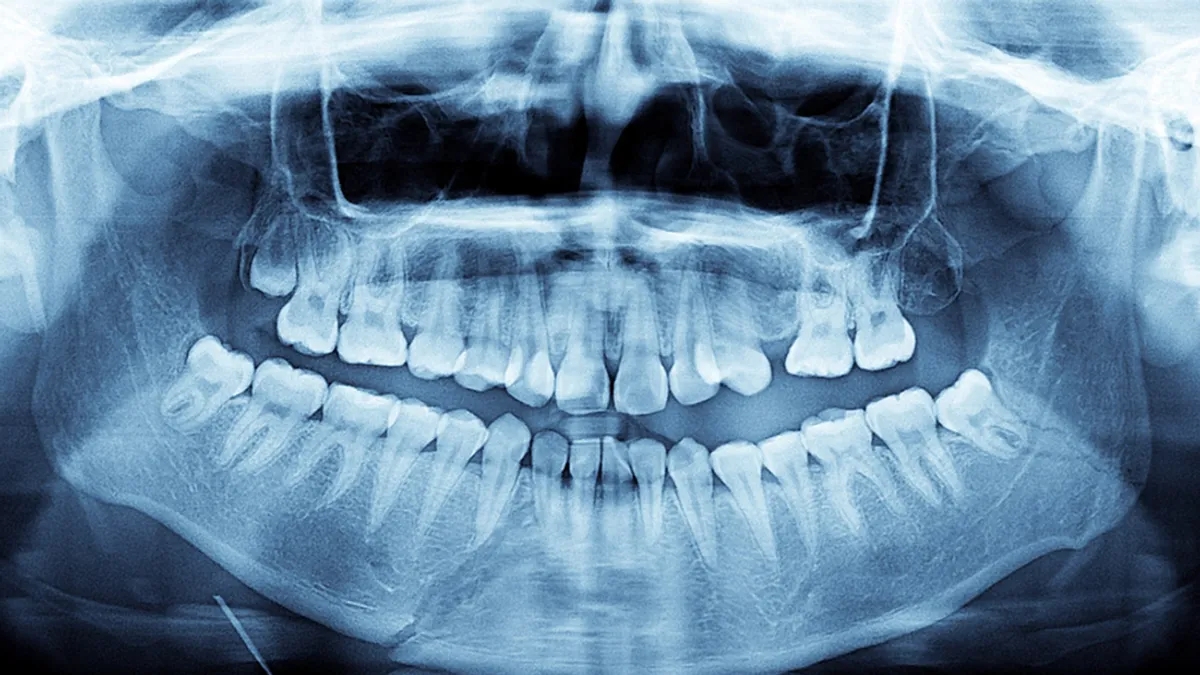

O dönemde 39 yaşında olan Prathab Muniandy, bir akşam ailesiyle yemek yerken dişlerinde farklılık olduğunu fark etti. Bunun üzerine ailesiyle birlikte dişlerini saymaya başladı. İlk sayımda ağzında 38 diş olduğu ortaya çıktı. Daha sonra çekilen röntgen görüntüleri ise henüz çıkmamış dört diş daha olduğunu gösterdi. Böylece Muniandy'nin toplam diş sayısının 42 olduğu anlaşıldı.

Uzmanlara göre normalden fazla dişe sahip olma durumu tıp dilinde "hiperdonti" olarak adlandırılıyor. Bu durum toplumda oldukça nadir görülüyor. Araştırmalara göre hiperdonti, insanların yaklaşık yüzde 0,1 ile yüzde 3,8'inde ortaya çıkabiliyor.